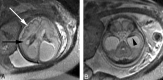

Fetal MR imaging is an increasingly available technique used to evaluate the fetal brain and spine. This is made possible by recent advances in technology, such as rapid pulse sequences, parallel imaging and advances in coil design. This provides a unique opportunity to evaluate processes that cannot be approached by any other current imaging technique and affords a unique opportunity for studying in vivo brain development and early diagnosis of congenital abnormalities inadequately visualized or undetectable by prenatal sonography. This 2-part review summarizes some of the latest developments in MR imaging of the fetal brain and spine and its application to prenatal diagnosis. This first part discusses the utility, safety, and technical aspects of fetal MR imaging, the appearance of normal fetal brain development, and the role of fetal MR imaging in the evaluation of fetal ventriculomegaly. The second part focuses on additional clinical applications of fetal MR imaging, including suspected abnormalities of the corpus callosum, malformations of cortical development, and spine abnormalities.